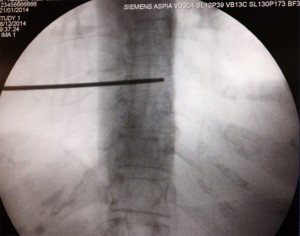

Se coloca al paciente en decúbito prono con una almohada debajo del tórax para magnificar la cifosis torácica y ampliar el sitio de entrada. Las manos se cruzan por encima de la cabeza del paciente, el cual tendrá la cabeza girada mirando hacia el lado contrario de la posición del médico. El paciente debe estar despierto, bien sea con sedación superficial o simplemente anestesia local si es colaborador. Se localiza el nivel afectado con una proyección en AP, identificando el punto de entrada en el espacio intervertebral. Luego se moviliza el rayo en el plano axial (cráneo-caudal) para ampliar el espacio intervertebral y borrar el doble contorno de los cuerpos vertebrales, y una vez hecho esto se marca el punto de entrada, que usualmente será 1-2 niveles por debajo del espacio intervertebral que se quiere alcanzar y 1 cm lateral a la apófisis espinosa (abordaje paramedial).

Se infiltra la piel con anestésico local (5-10 ml de lidocaína 1%) y después se hace la técnica epidural con una aguja tuohy 18-20G. Después de atravesar la piel se avanza la aguja inclinándola levemente hacia superior y medial para hacer contacto con la lámina. Una vez alcanzada la lámina se retira el fiador y se conecta la jeringa de baja resistencia; luego se redirige la aguja dándole una angulación de 45° en el plano sagital y 15° hacia medial; antes de avanzar se debe comprobar con el rayo en lateral que la aguja se encuentra entre las dos apófisis espinosas. Se recomienda también seguir avanzando lentamente y con guía fluoroscópica para evitar el daño medular directo con la aguja.

Una vez se nota la pérdida de resistencia se inyecta contraste y se debe dibujar una línea en la base de ambos procesos espinosos, con el rayo aún en posición lateral.